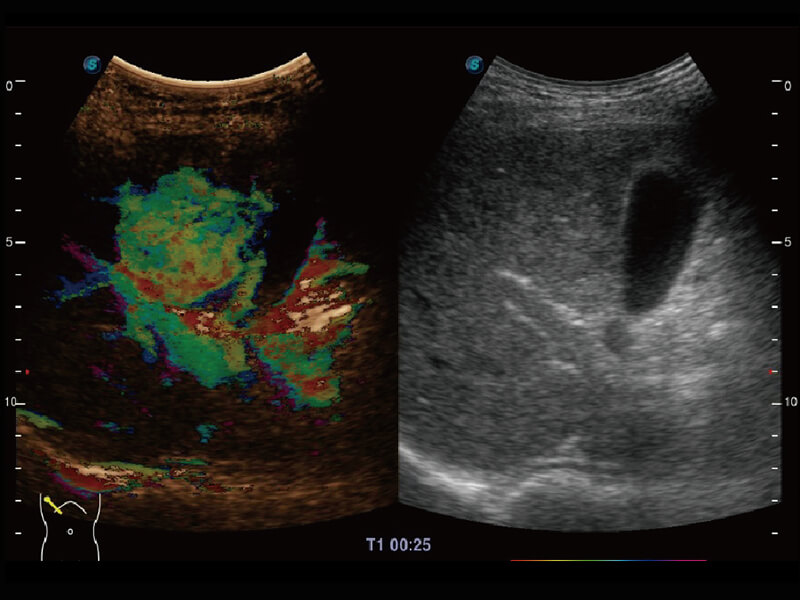

成像功能

性能优异的硬件架构,极大提升超声系统的运行效率和数据处理能力。相比以往超声成像系统,Wis+平台为您带来极快的响应速度和成像帧频,提升检查流畅度。